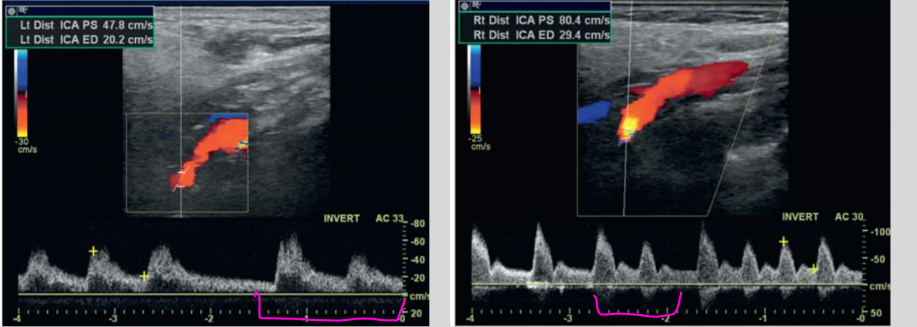

what is this waveform showing?

Cardiac Arrythmia: irregular heartbeat

Cardiac Arrythmia